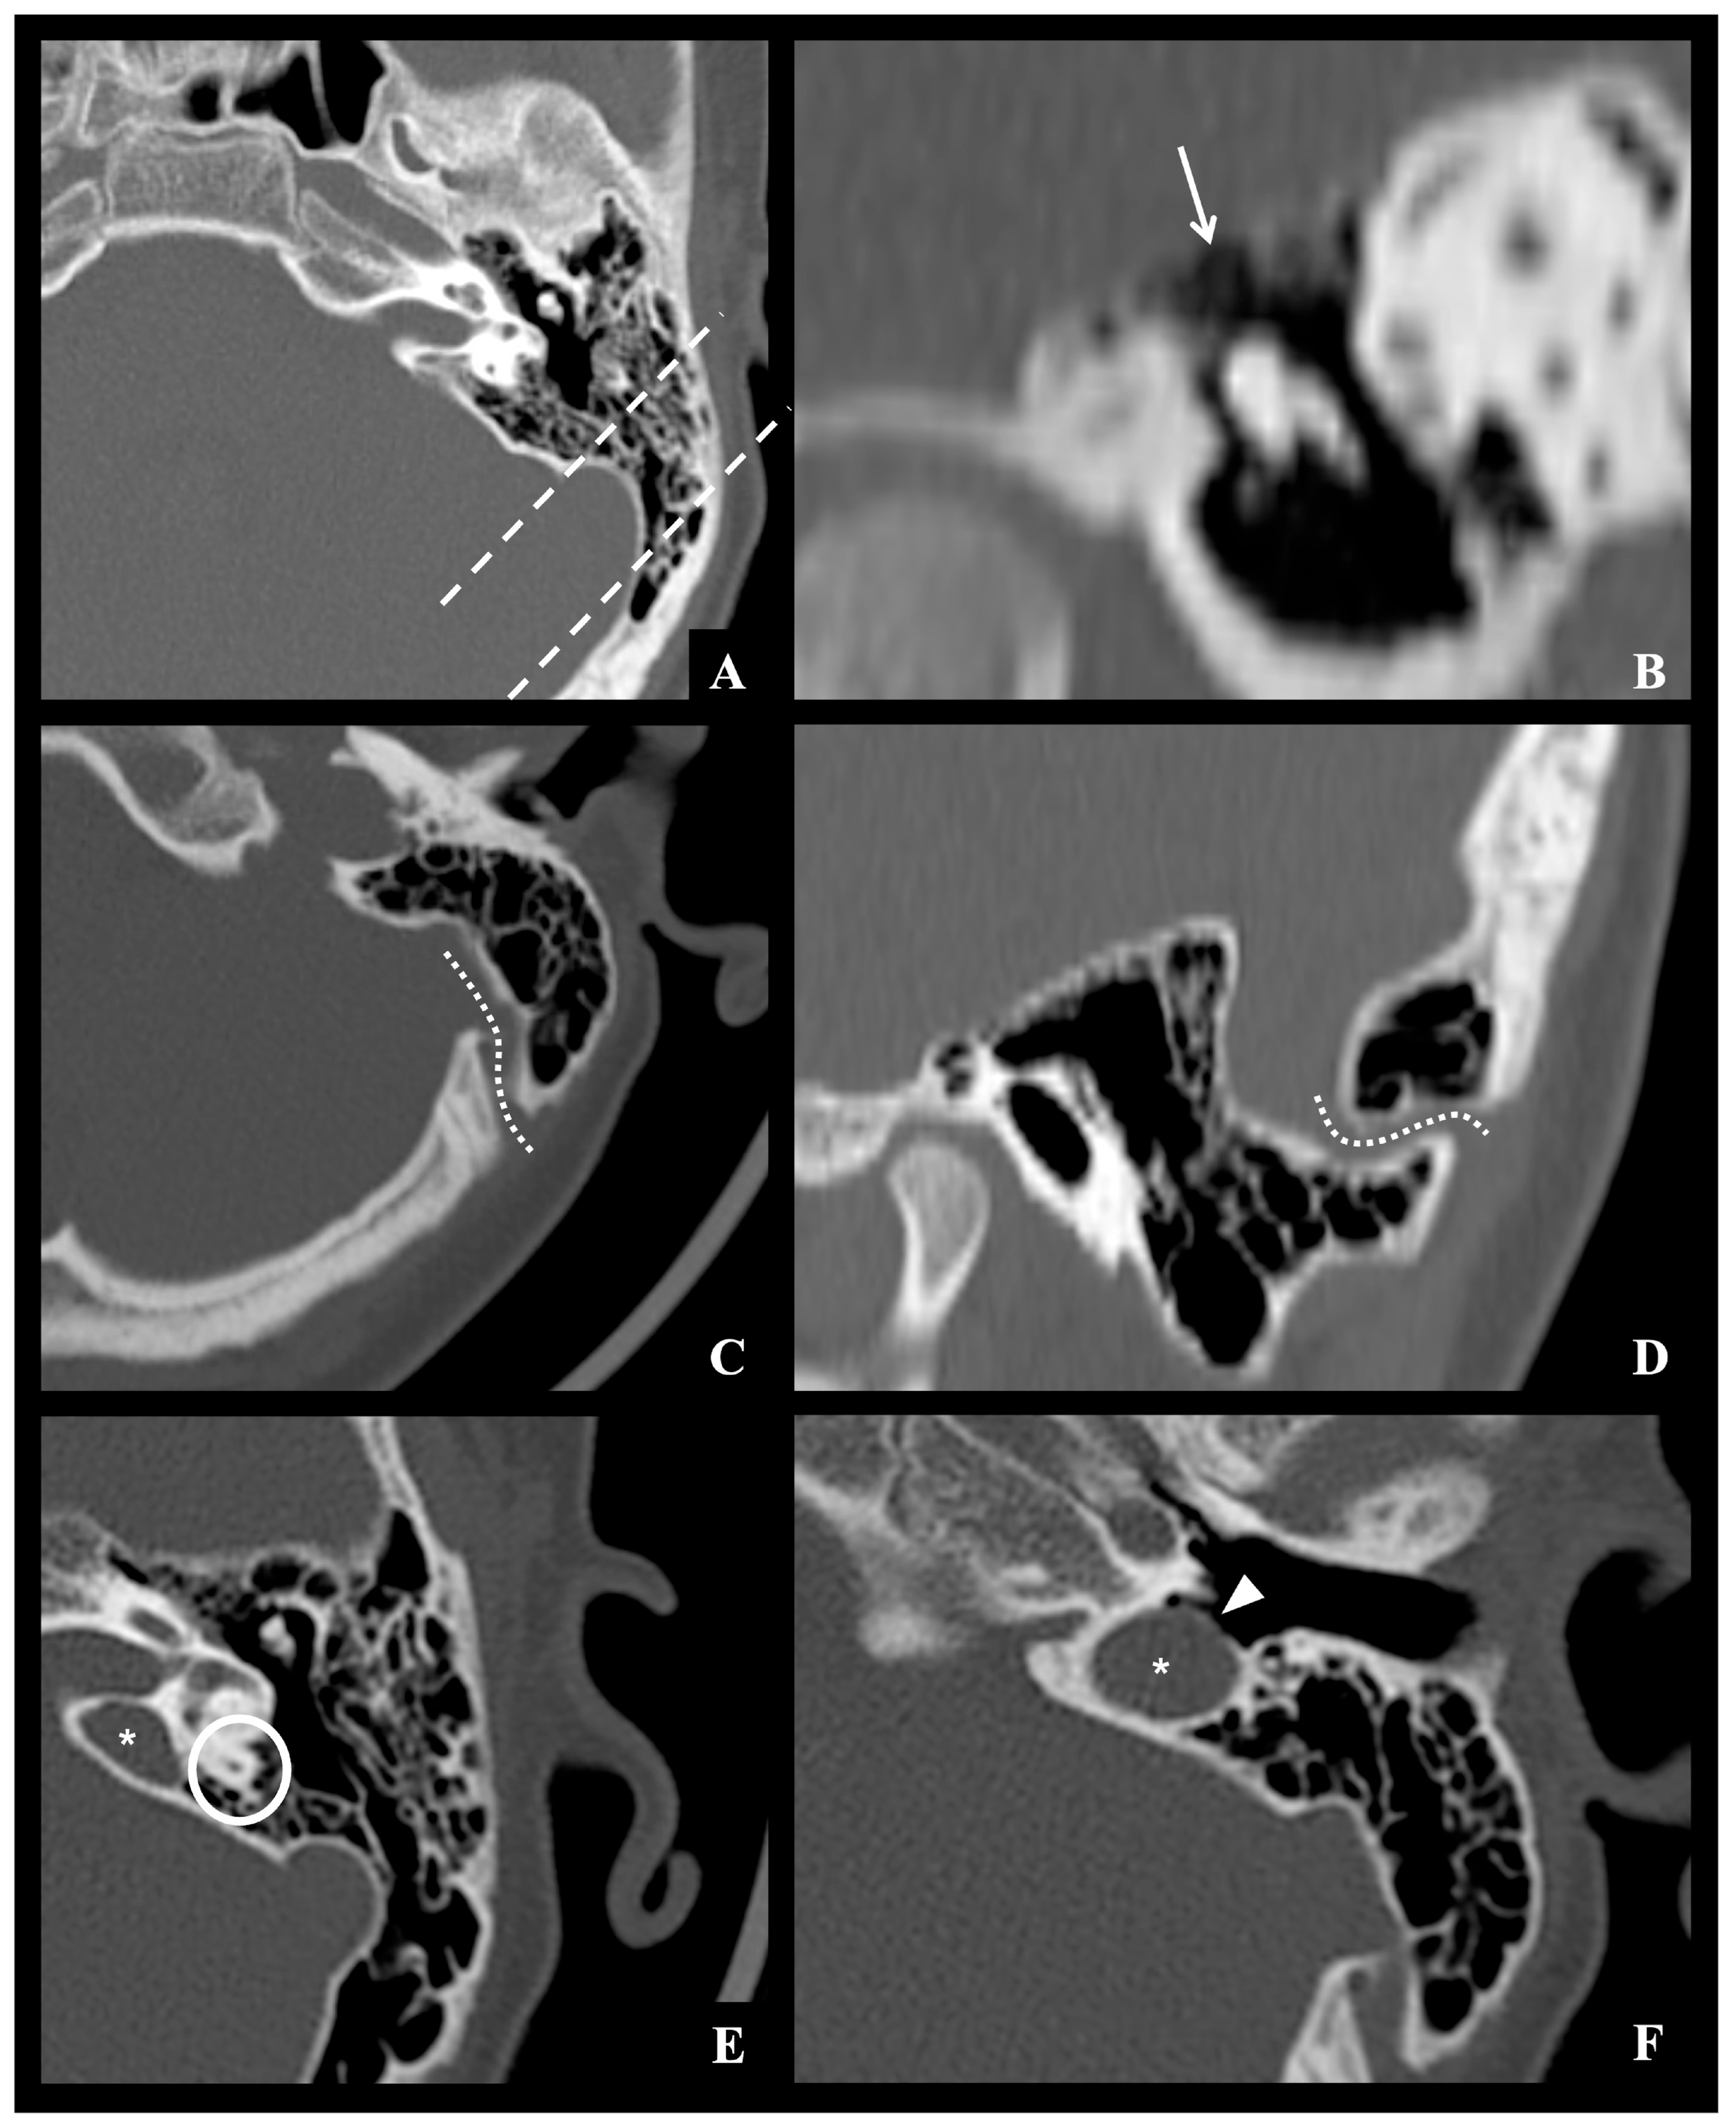

All neuroradiological images were re-evaluated in consensus by two experienced neuroradiologists to identify normal anatomical variants potentially considered predisposing or facilitating the intracranial spread of infection from the otomastoid region. Specifically, these factors were classified as follows: (1) vascular variants involving course, or position of the sigmoid–jugular sinus complex and/or the presence of aberrant mastoid emissary veins (defined as a transosseous connection between the sigmoid dural venous sinus and the suboccipital venous plexus); (2) variants in the thickness of the tegmen tympani; and (3) pneumatization variants, including hyperpneumatization of mastoid air cell compartments and/or the presence of accessory air cells in retroauricular or perilabyrinthine locations. Cases in which inflammatory bone destruction obscured or mimicked normal anatomical variants were carefully reviewed in consensus by two experienced neuroradiologists, and when diagnostic uncertainty persisted, they were excluded from morphometric analysis. An example of the considered anatomical variants is shown in Figure 2.

Figure 2. Example of normal mastoid anatomical variants observed on the left side in a same 11-year-old male control patient undergone brain CT examination due to traffic injury: (A) grade IV mastoid hyperpneumatization according to Han et al., with air cells extending beyond the sigmoid sinus posteriorly (dashed lines); (B) thinned tegmen tympani (white arrow); (C,D) accessory mastoid emissary vein enlargement (dotted lines); (E,F) high riding jugular bulb type 4 according to Manjila et al. classification (star), located above the inferior margin of the posterior semicircular canal (white circle), with dehiscent sigmoid plate protruding into middle ear (white arrowhead).